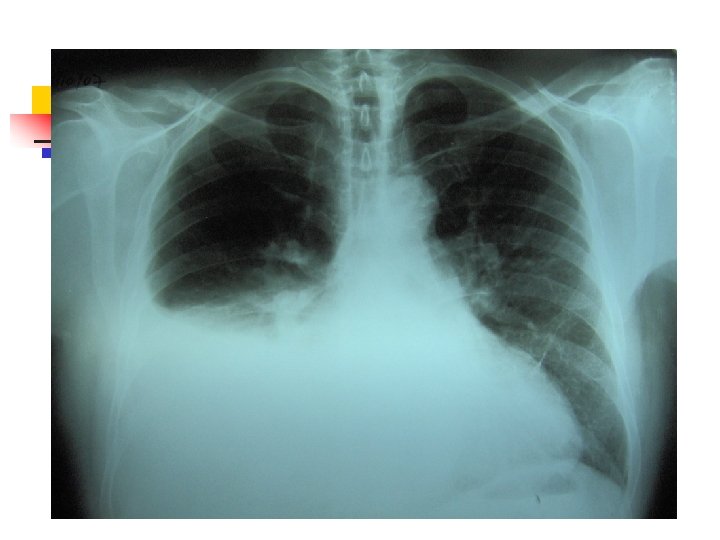

Aproximación diagnóstica: Radiología n n n 250 ml son necesarios para provocar alteraciones radiológicas. Primer signo: Borramiento del SCD Damoisseau. Desviación de estructuras. Derrame tabicado.